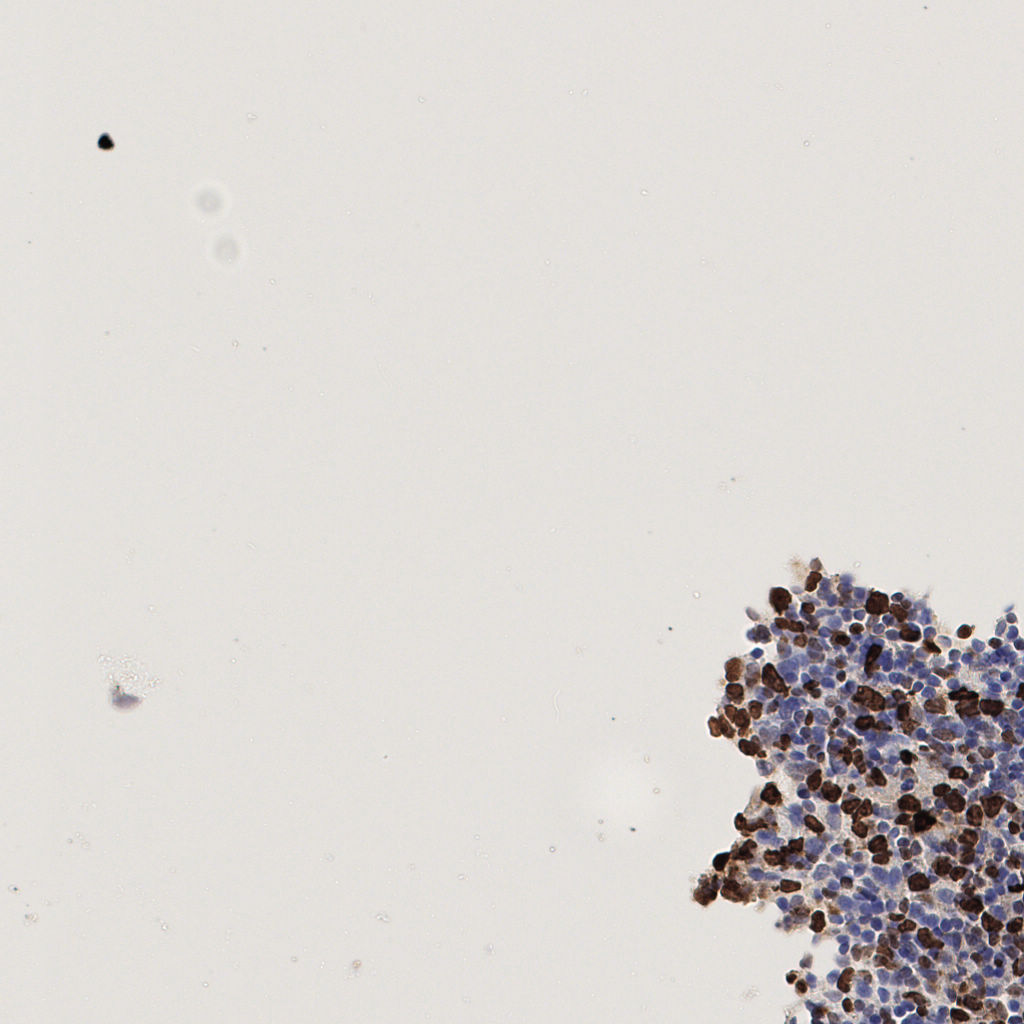

7.85%

Ki67 指数

阴 1104

阳 94

标记后

标记前